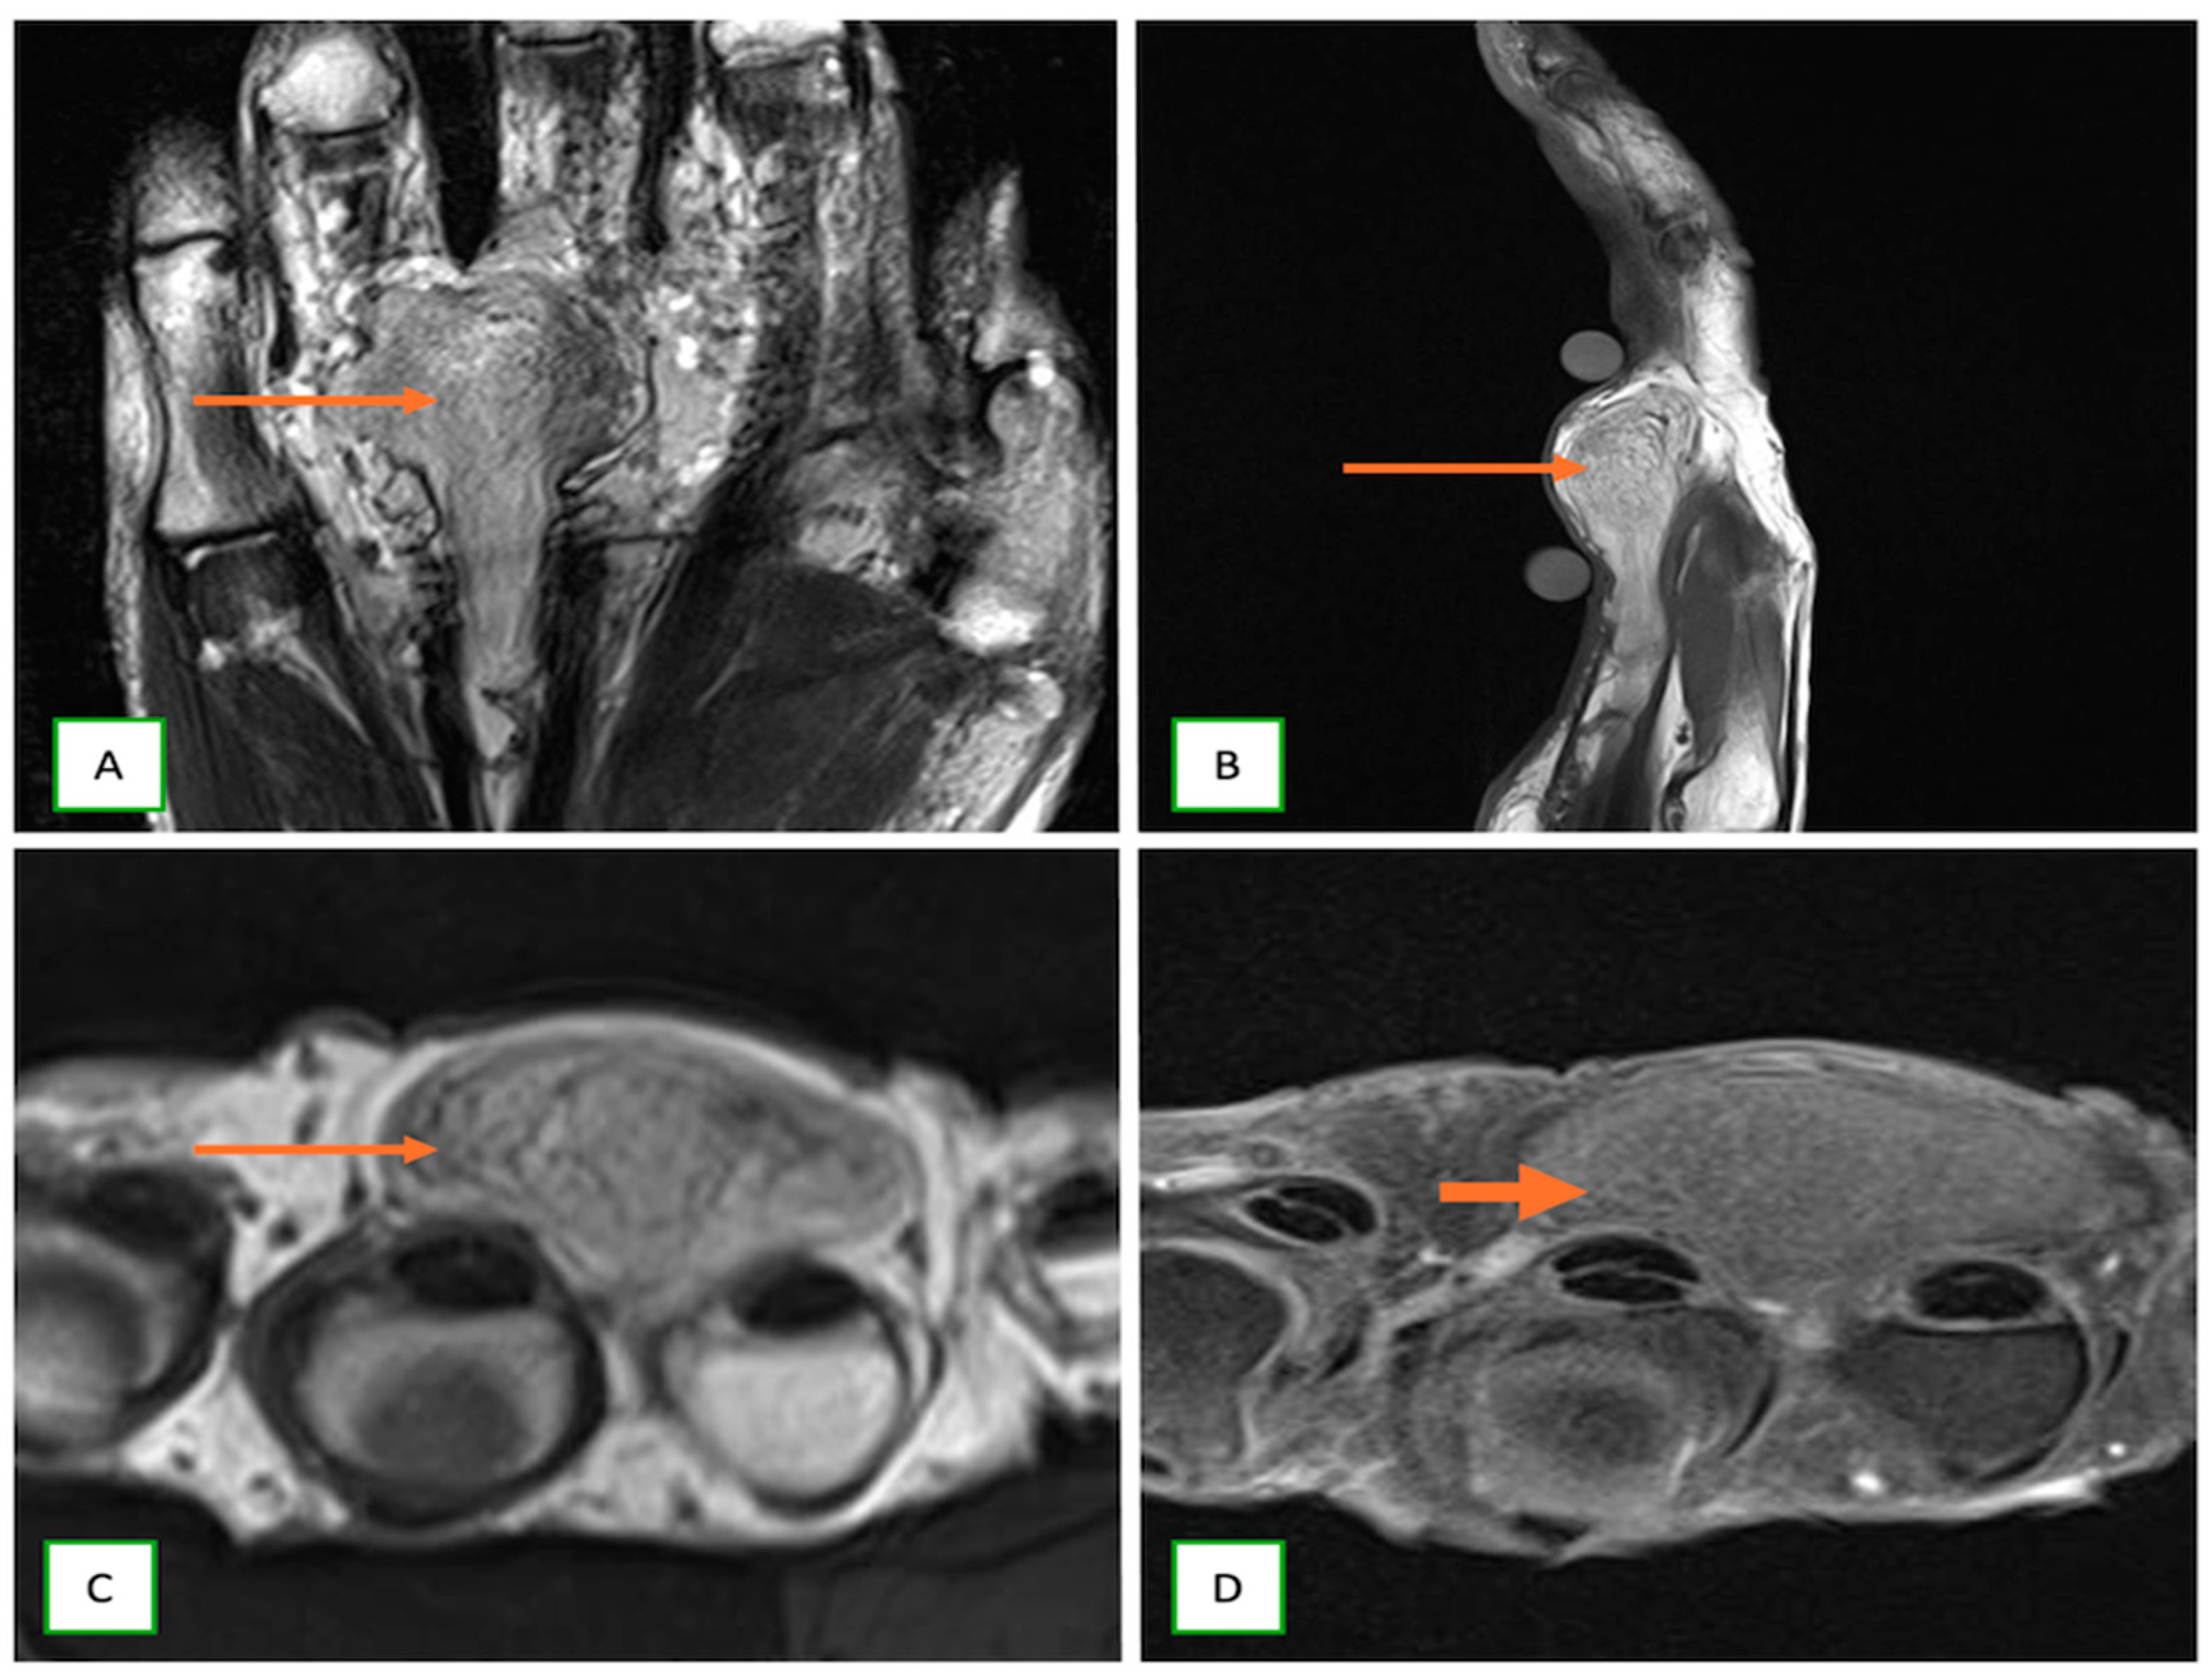

- Wilson, T.J.; Howe, B.M.; Stewart, S.A.; Spinner, R.J.; Amrami, K.K. Clinicoradiological features of intraneural perineuriomas obviate the need for tissue diagnosis. J. Neurosurg. 2018, 129, 1034–1040. [Google Scholar] [CrossRef] [PubMed]